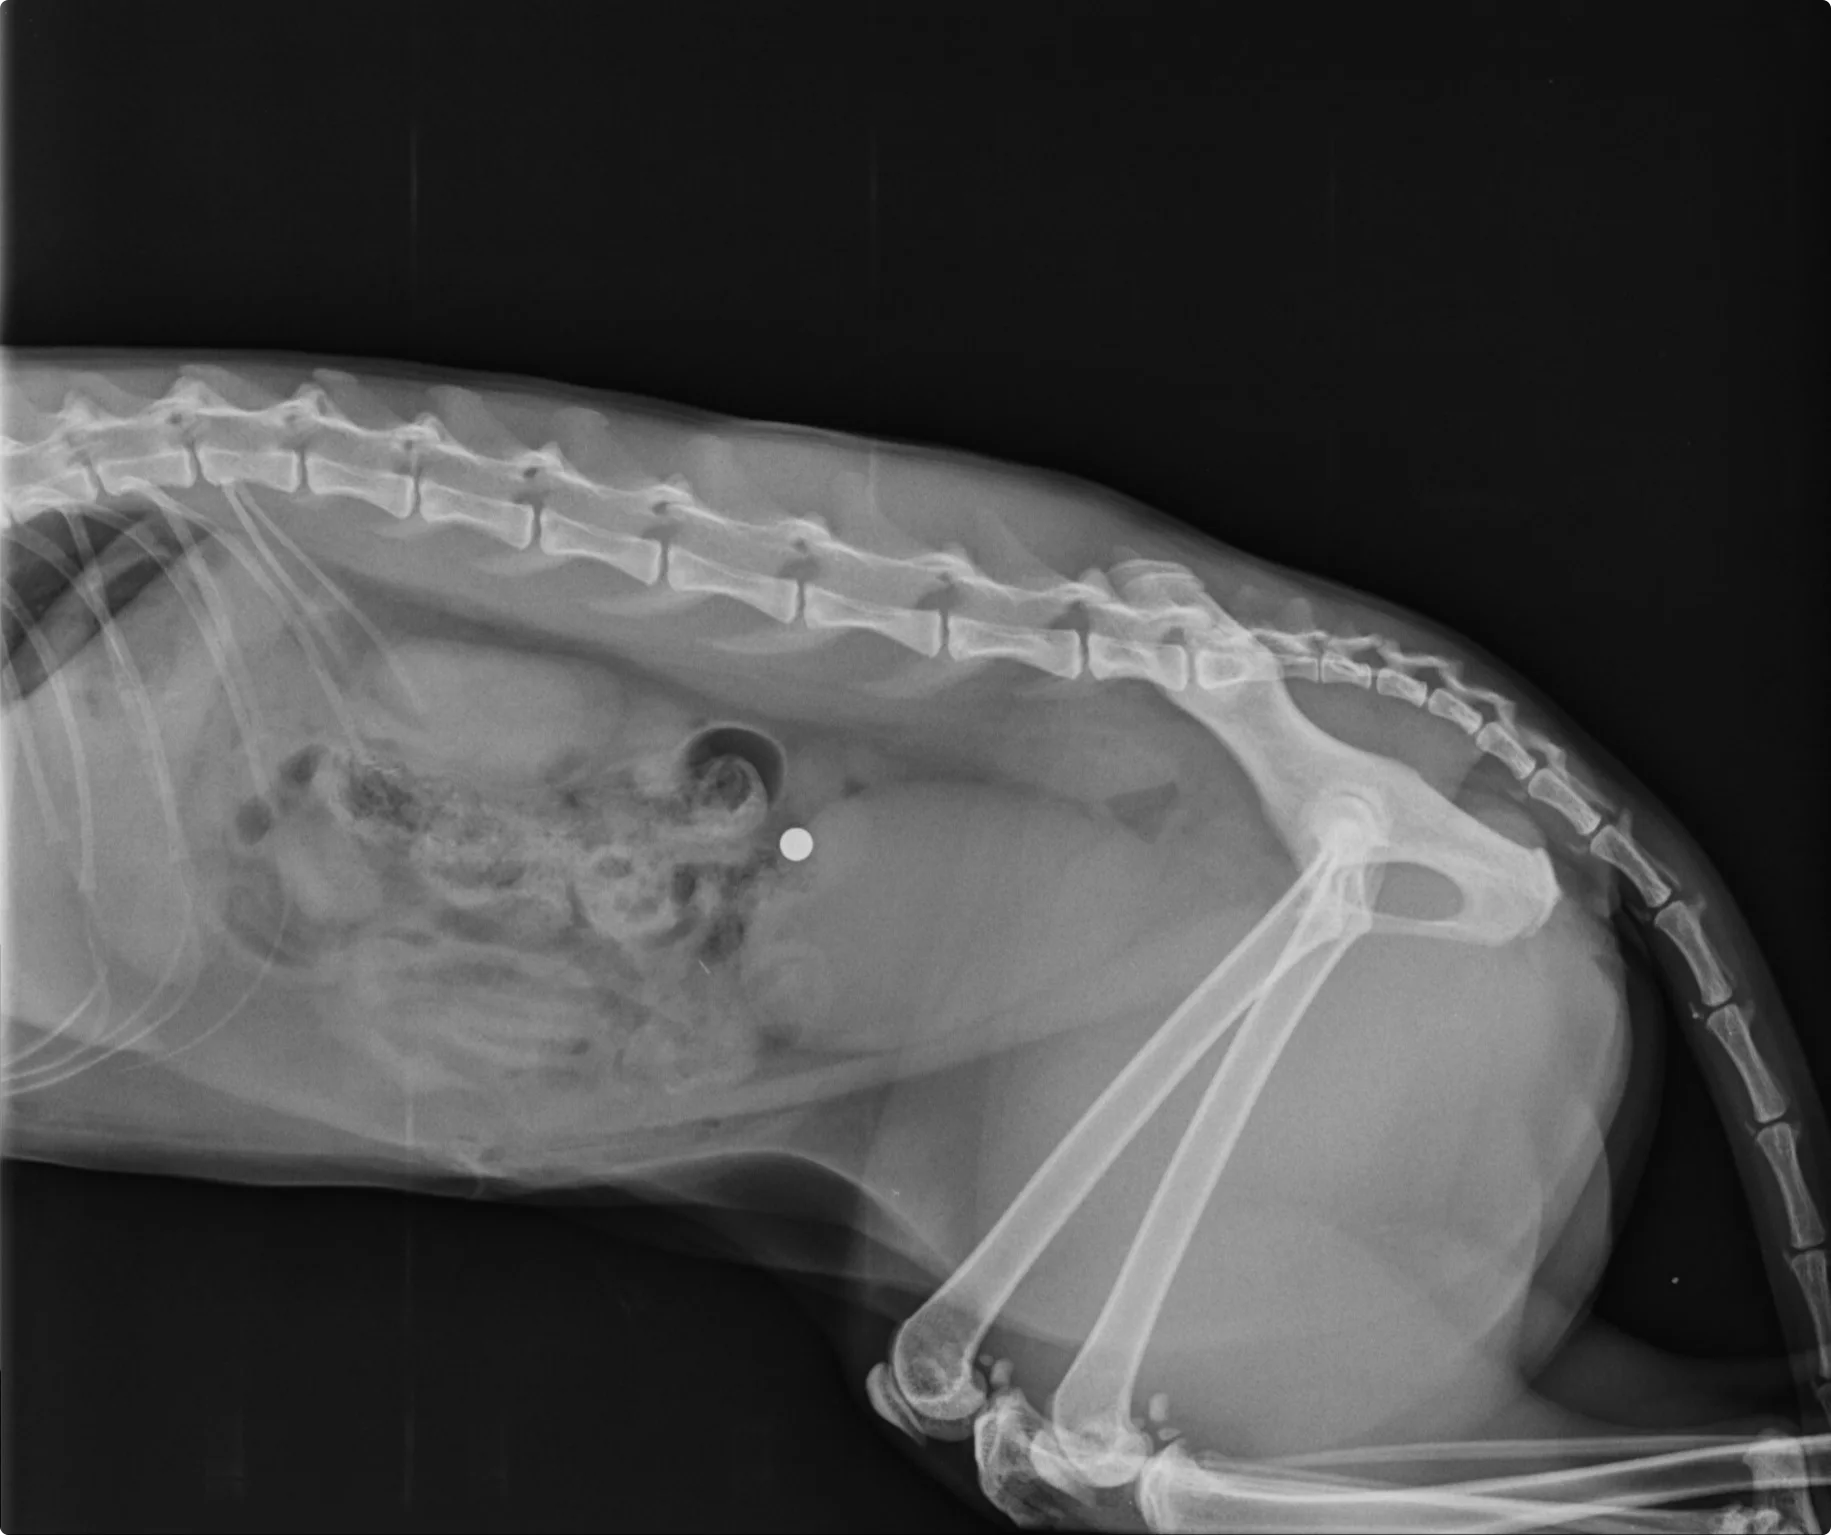

"Ze had zo'n pijn en omdat het ook zo bloedde vermoedde ik dat het dieper was dan alleen een oppervlakkig wondje van een gevecht met een andere kat. Want dat is ook een klein rond gaatje." Ze besluit een röntgenfoto te maken om te kijken wat de schade van binnen precies is.

Op de röntgenfoto is heel duidelijk een metalen balletje te zien. "Ik dacht nog: dit lijkt ontzettend op een kogel", gaat Nielsen verder. "Maar dat geloofde ik niet. Of ik wilde het niet geloven." Ze maken nog een foto, maar dan vanuit een andere hoek om zo een 3D-beeld te krijgen van de buik.

"Toen zagen we dat de kogel aan de rechterkant van de buik zat. We hebben daarna zelfs een foto gemaakt van de röntgenplaat om zeker te weten dat het geen afwijking was op de plaat." Want dit betekent dat de kogel zich een weg van de linker- naar de rechterkant van de buik heeft gebaand. "En dat het van binnen foute boel is."

De röntgenfoto van Bo. Beeld: Dierendokter Zandvoort